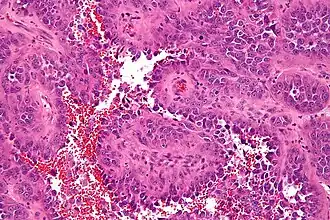

| Micrografia de um angiossarcoma. coloração H&E. | |

Uma vez que as células cancerígenas podem ser transportadas pelo sangue ou fluxo linfático, angiossarcomas podem mais facilmente metatizar para sítios distantes, particularmente o fígado e os pulmões.[3] A maioria dos tumores viscerais de parede de vasos sanguíneos e linfáticos são cancerosos (malignos). Hemangiossarcomas e linfangiossarcomas da pele não são comuns.[4] O sarcoma de Kaposi é um tipo de câncer que também é oriundo de células endoteliais.[5] Angiossarcomas mostram sinais de hemorragia e necrose. Patologicamente, células tumorais mostram maior relação núcleo-citoplasma, hipercromasia nuclear, pleomorfismo nuclear e alta atividade mitótica.[6]